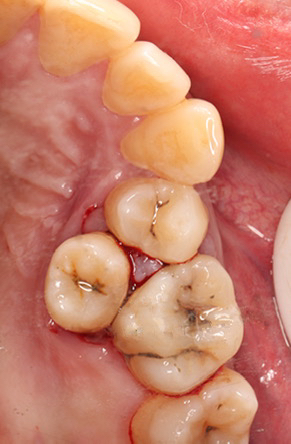

1. 清洁困难,引发龋病与牙周炎

弓外牙位置异常,日常刷牙难以清洁到位,容易堆积食物残渣与牙菌斑,不仅自身易蛀坏,更会牵连邻牙,形成难以清理的“卫生死角”,显著增加邻牙龋坏和牙周感染的风险。

邻牙已龋坏